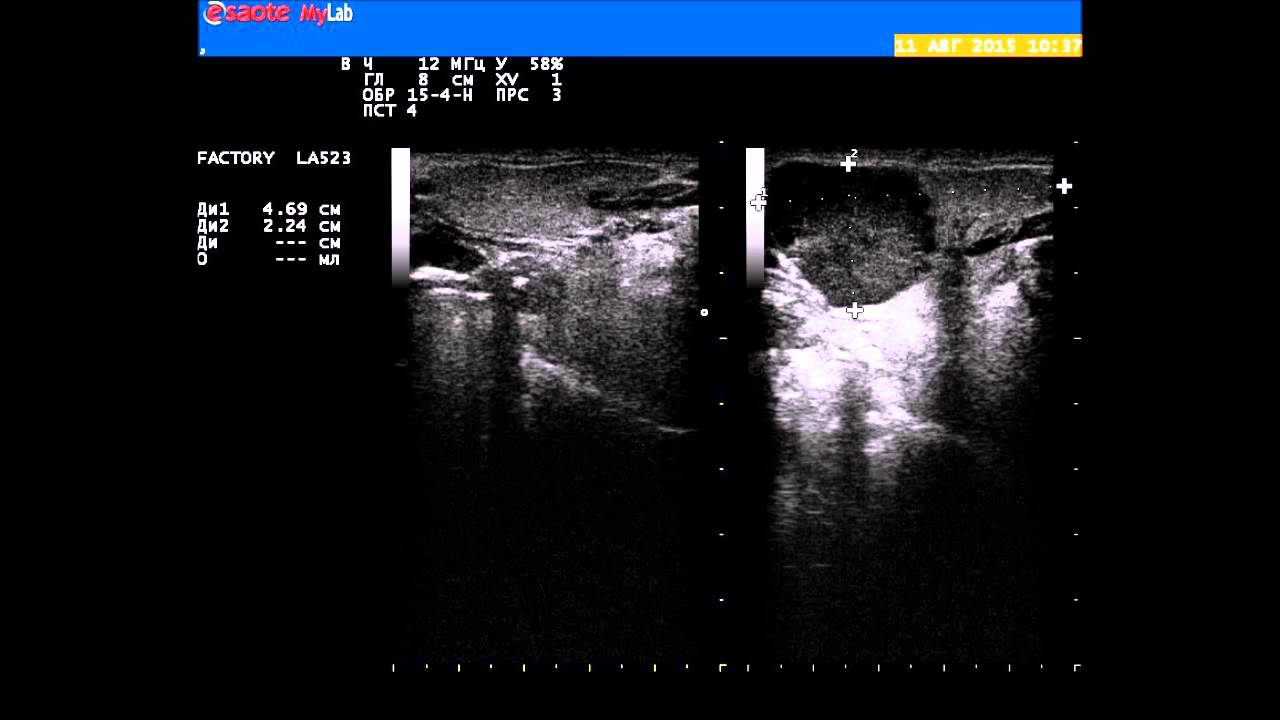

Так называемые муцинозные и серозные опухоли также достаточно часто претерпевают злокачественное перерождение. Это очень точный метод, который позволяет определять размеры узлов вплоть до десятых долей миллиметра.

Это очень точный метод, который позволяет определять размеры узлов вплоть до десятых долей миллиметра. В последние годы отмечается рост числа случаев заболеваний шейки матки у молодых женщин.